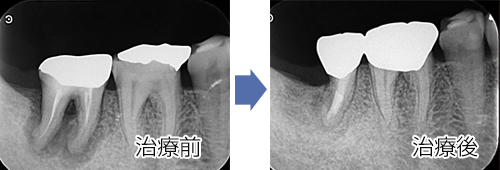

歯科用レーザーといっても数種類のレーザーが存在します。

当院で使用しているレーザーは組織浸透性が高く、根尖病巣(根の病気)や重度歯周病等に高い効果を期待できます。また口内炎等においても患者様から高い評価を頂いております。

レーザーをあてることで骨の組織が再生しているのがわかります。